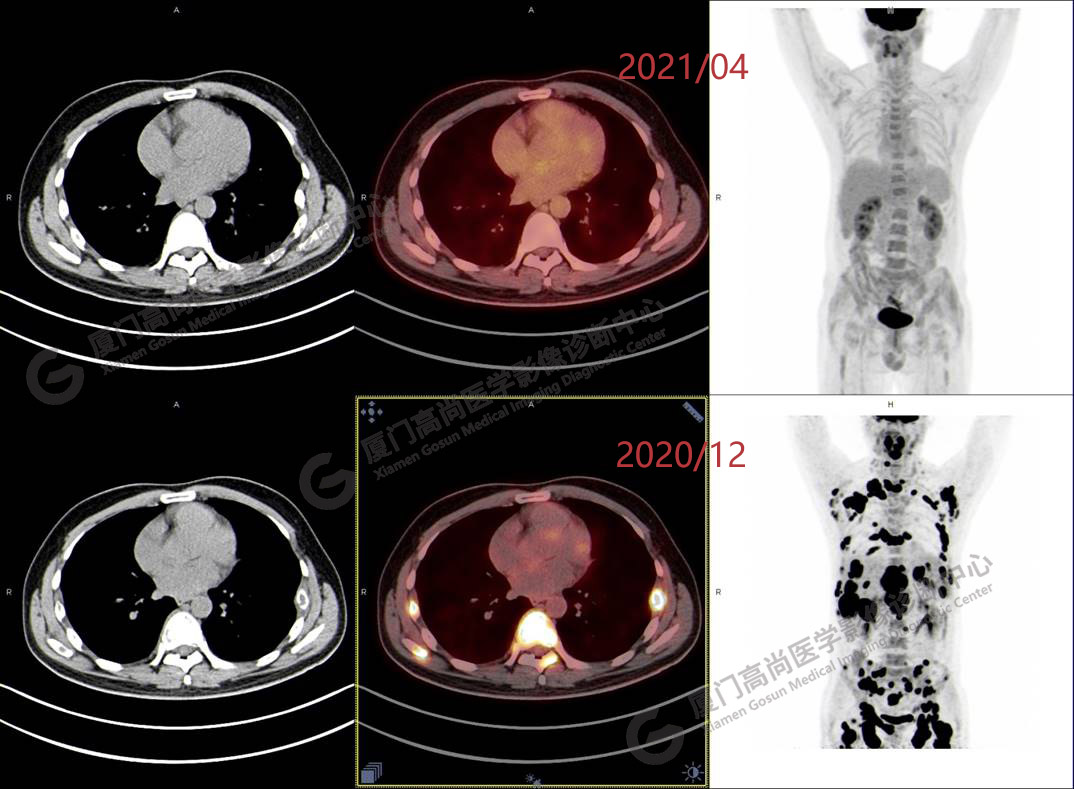

2020.12月本中心PET/CT示:全身多發(fā)腫大淋巴結(jié),代謝不同程度增高;肝臟多發(fā)稍高密度結(jié)節(jié)、脾臟多發(fā)稍低密度結(jié)節(jié),代謝異常增高;全身多發(fā)骨骼溶骨性骨質(zhì)破壞,代謝異常增高,胸2、腰1椎體病理性骨折,診斷為淋巴瘤。隨后,病理確診為彌漫大B細(xì)胞淋巴瘤。

患者化療4個(gè)療程后,于2021.04月返我中心復(fù)查,現(xiàn)患者本人已能自主行走,此次更是獨(dú)自一人來我中心復(fù)查PET/CT。檢查結(jié)果顯示:原全身多發(fā)病灶基本消失,且病灶代謝基本恢復(fù)正常。以下是患者PET/CT前后對(duì)比圖像:

PET/CT前后對(duì)比圖像1